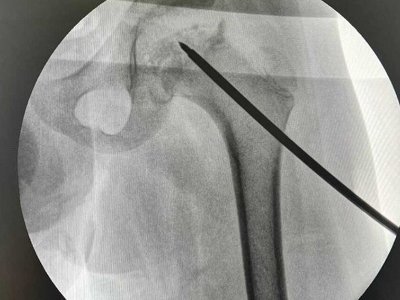

Пацієнту - 9 років: зробили першу малоінвазивну операцію дитині з хворобою Пертеса